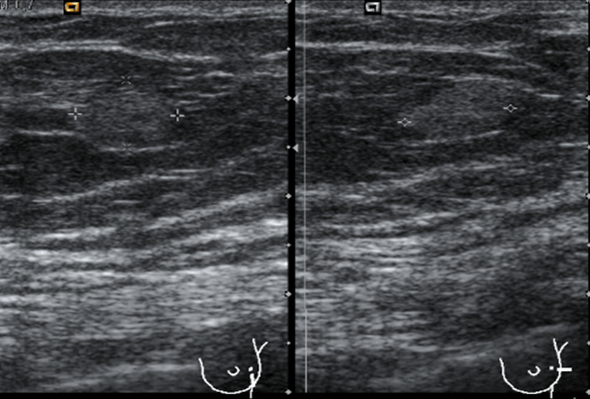

Las medidas tanto en transverso como en longitudinal, imagen 3 y 4 son importantísimas, hemos hablado anteriormente que la medida tiene relación directa con el diagnóstico diferencial de estas patología tumorales, y como no, la vascularización, que la ves en la imagen número 5 y que está aumentada, usaremos doppler color, imagen 5, y doppler power, imagen 6.

Te pido ahora que observes aténtamente la imagen 7 y la imagen 8 y en las lesiones marcadas con flechas amarillas. En la imagen 7 puedes ver imágenes nodulares en ambos lóbulos tiroideos, son nódulos de los que habitualmente encontramos en un bocio multinodular, compara ahora con la imagen de la imagen 8, así a bote pronto, ¿Te llama algo la atención?…mira bien las imágenes…tómate un momento, no sigas leyendo…

Sí, efectivamente, la lesión de la imagen 8, que es a la que le hemos estado dedicando este tiempo, parece estar localizada fuera del tiroides, en su LTD, concretamente en su porción más profunda, como pegada a él…aunque el aspecto pueda ser similar a un nódulo normal, en este caso, la localización de la lesión, también nos va a ayudar en el diagnóstico.